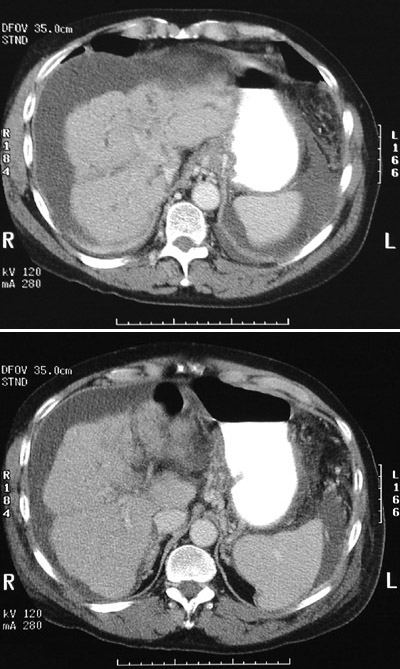

![]() | In these two views from an abdominal CT scan are prominent dilated collateral vessels in the region of the gastroesophageal junction in a patient with a small, nodular shrunken liver with cirrhosis. Cirrhosis has led to portal hypertension and varices as well as to ascites with abdominal fluid collections. This patient had ulcerative colitis and developed primary sclerosing cholangitis. This patient is postoperative following colectomy. |